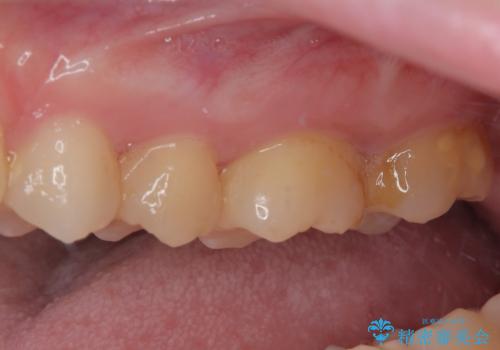

奥歯のむし歯が痛い セラミックによるむし歯治療

- 奥歯に激痛が走り近医を受診したところ、根管治療が必要とのことで、当院での治療を希望して来院された患者様です。

奥歯2歯の間からむし歯が広がったようで、最後方歯は既に神経が失活している状態で、手前の歯は神経組織に問題はないものの速やかに処置が必要な状態でした。

最後方歯は根管治療を行った上でオールセラミッククラウンにて補綴治療を行うこととし、手前の歯はセラミックインレーにて修復治療を行うこととしました。